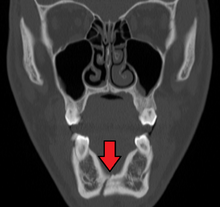

Computed tomography

Computed tomography is the most sensitive and specific of the imaging techniques. The facial bones can be visualized as slices through the skeletal in either the axial, coronal or sagittal planes. Images can be reconstructed into a 3-dimensional view, to give a better sense of the displacement of various fragments. 3D reconstruction, however, can mask smaller fractures owing to volume averaging, scatter artifact and surrounding structures simply blocking the view of underlying areas.

Research has shown that panoramic radiography is similar to computed tomography in its diagnostic accuracy for mandible fractures and both are more accurate than plain film radiograph.[11] The indications to use CT for mandible fracture vary by region, but it does not seem to add to diagnosis or treatment planning except for comminuted or avulsive type fractures,[12] although, there is better clinician agreement on the location and absence of fractures with CT compared to panoramic radiography.[13]